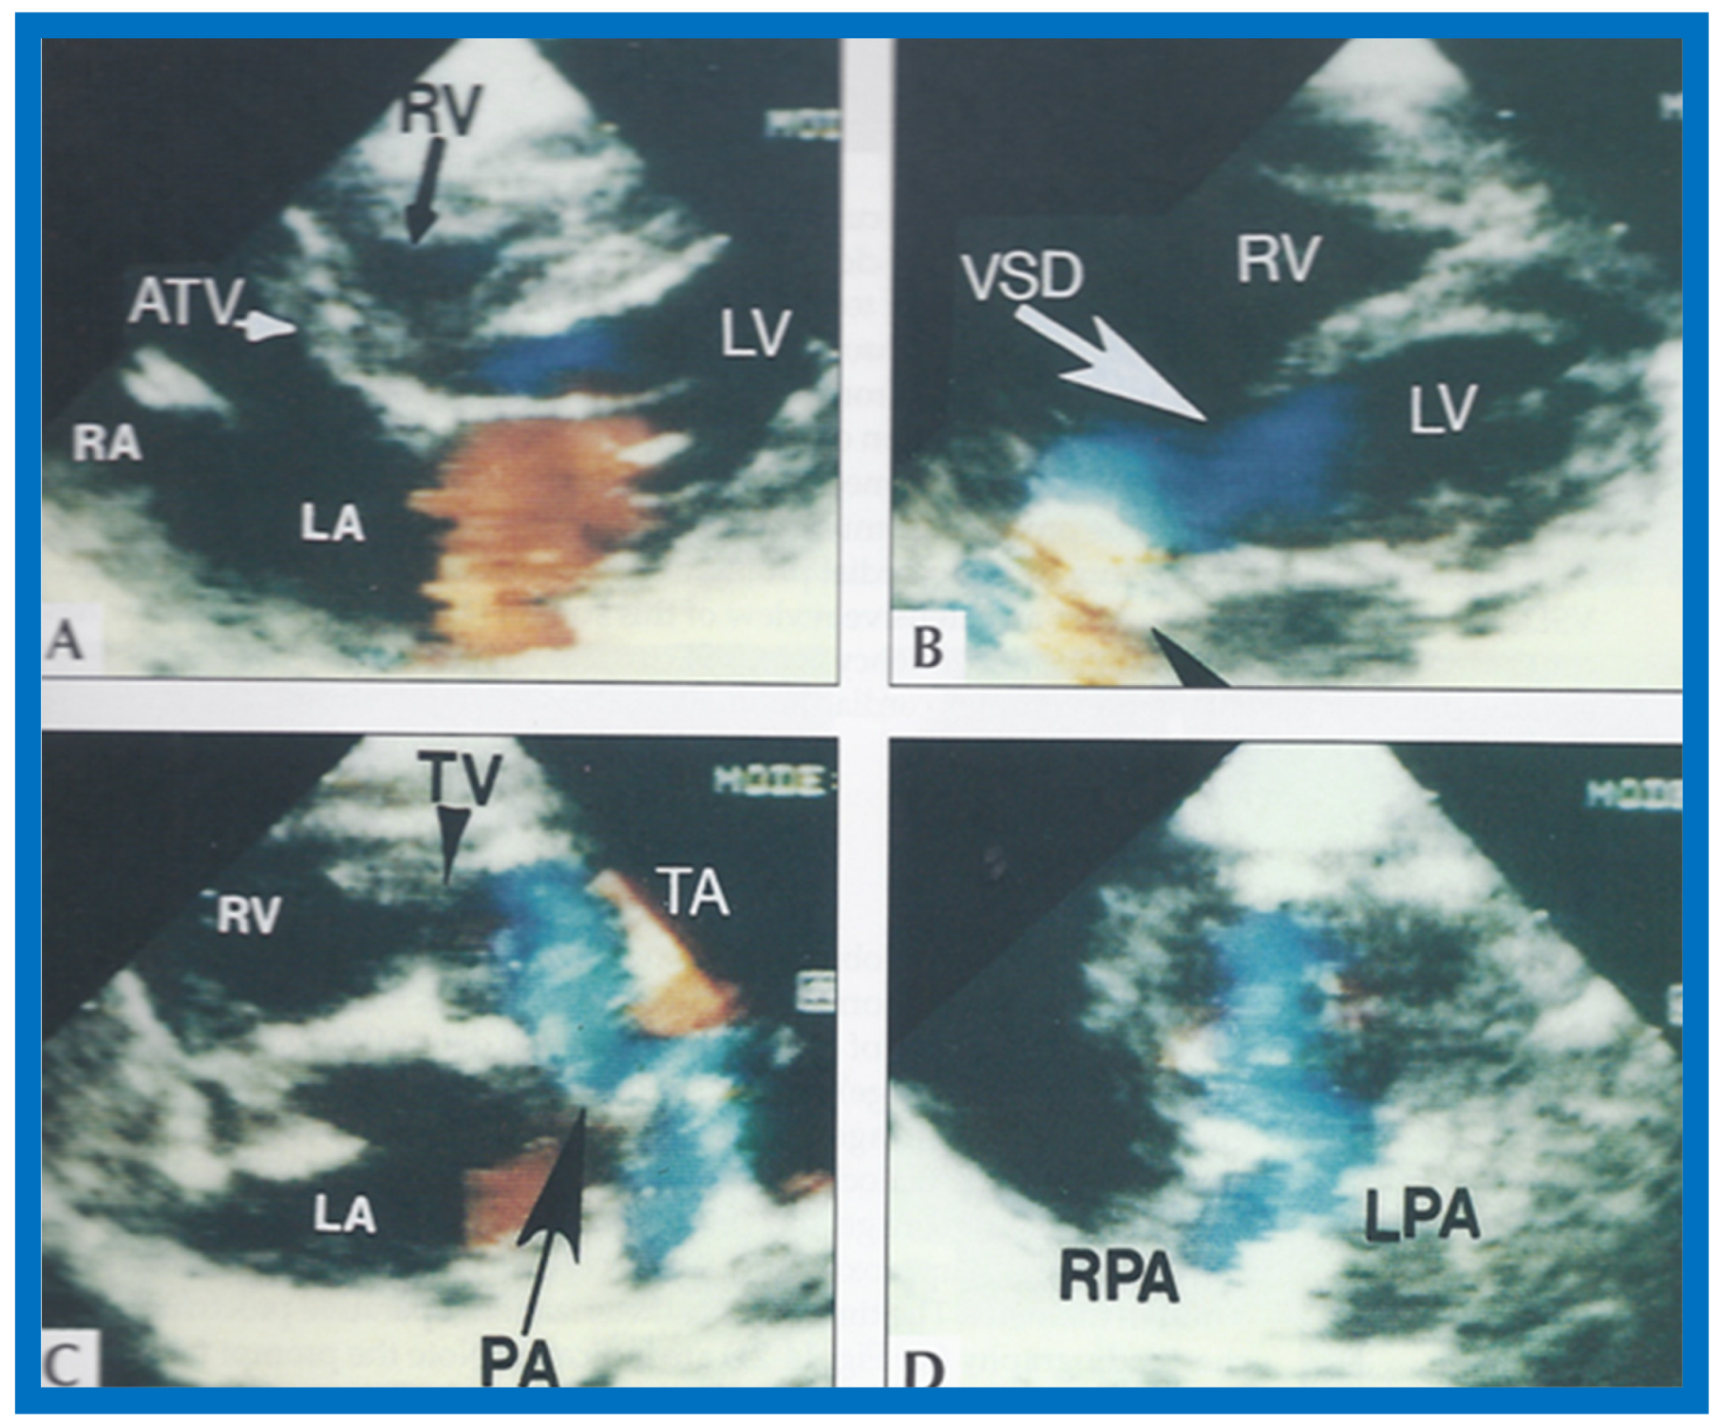

Figure 24.

Video frame from a two-dimensional echocardiographic and color Doppler study demonstrating (A) atretic tricuspid valve (ATV) between the right atrium (RA) and right ventricle (RV) and blood flow from the left atrium (LA) into the left ventricle (LV) across the mitral valve. The RV (arrow) is very small and hypoplastic. (B) LV and RV with a large ventricular septal defect (VSD) below the truncus arteriosus (TA). Turbulent flow across the truncal valve suggests truncal valve stenosis. (C) origin of the pulmonary artery (PA) from the TA by color flow (arrow), and (D) division of right (RPA) and left (LPA) pulmonary arteries from the PA (labeled in d) in a short-axis view. TV, truncal valve leaflets. Reproduced from Rao P.S., et al. [22].